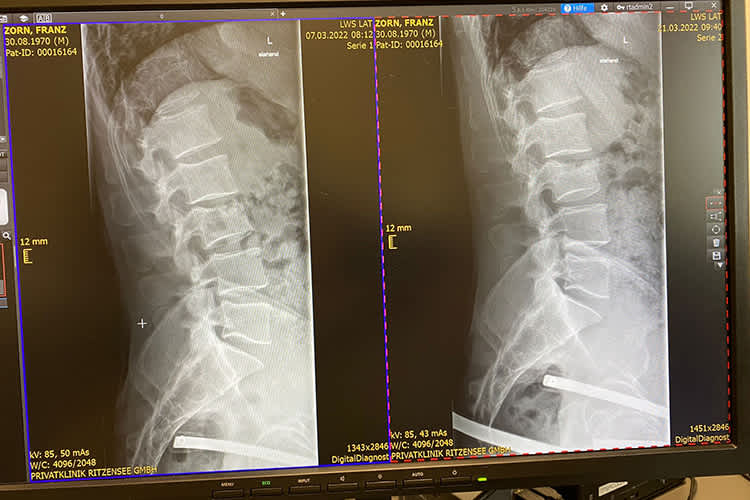

Franz Zorn musste nach seiner Wirbelverletzung das Finalrennen zur Eisspeedway-Europameisterschaft absagen. Auch bei den letzten Rennen zur Eisspeedway-WM Anfang April muss der Österreicher passen.

Für Zorn ist somit die Saison 2022, in der er von mehreren Verletzungen geplagt wurde, frühzeitig beendet. Der Saalfeldener fuhr Rennen in Schweden, Polen und Russland und hatte bei den Prädikatsrennen mehrfach das Pech, in Stürze verwickelt zu werden. Beim EM-Rennen im Dezember 2021 stürzte Zorn im Training und beim WM-Rennen in Togliatti und dem ersten Finalrennen zur Eisspeedway EM 2022 in Sanok crashte er unverschuldet.